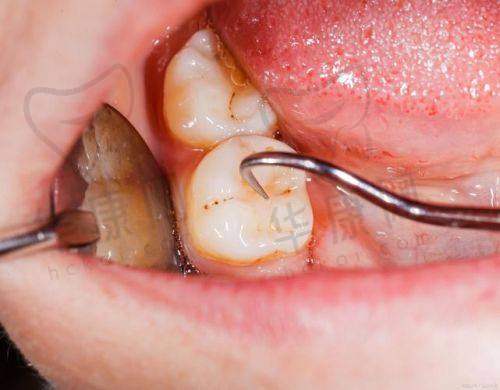

江宁牙管家口腔推出的阻生智齿拔除641元起的优惠活动,吸引了众多有智齿困扰的市民关注。阻生智齿不仅会引发疼痛,还可能影响口腔健康,及时拔除至关重要。那么江宁牙管家口腔在阻生智齿拔除方面究竟有何优势呢?下面为您详细介绍。

江宁牙管家口腔此次推出的阻生智齿拔除641元起的价格,是根据智齿的生长情况和拔除难度来定价的。一般来说,智齿位置比较正,拔除难度较低的,费用可能在500 - 1000元之间;而如果智齿是阻生齿或者位置较深,需要切开牙龈或磨除部分牙槽骨,费用会高一些,大概在1000 - 3000元不等。这种灵活的定价方式,能够让患者根据自身情况选择合适的治疗方案,既确保了治疗成效,又能在一定程度上减轻患者的经济负担。